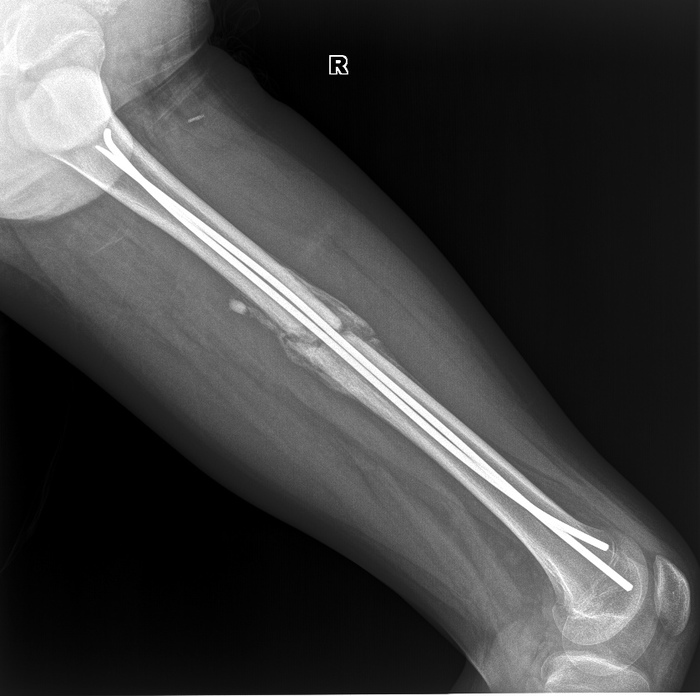

Ребенок 13 лет, перелом бедренной кости. Вставили два тена. Как видно, эндостальная консолидация (сращение внутри кости) слабо выражена, зато резко выраженная периостальная консолидация (костная мозоль вокруг перелома).

И вот еще один снимок с разницей почти в 4 месяца, видно, что срослось хорошо.